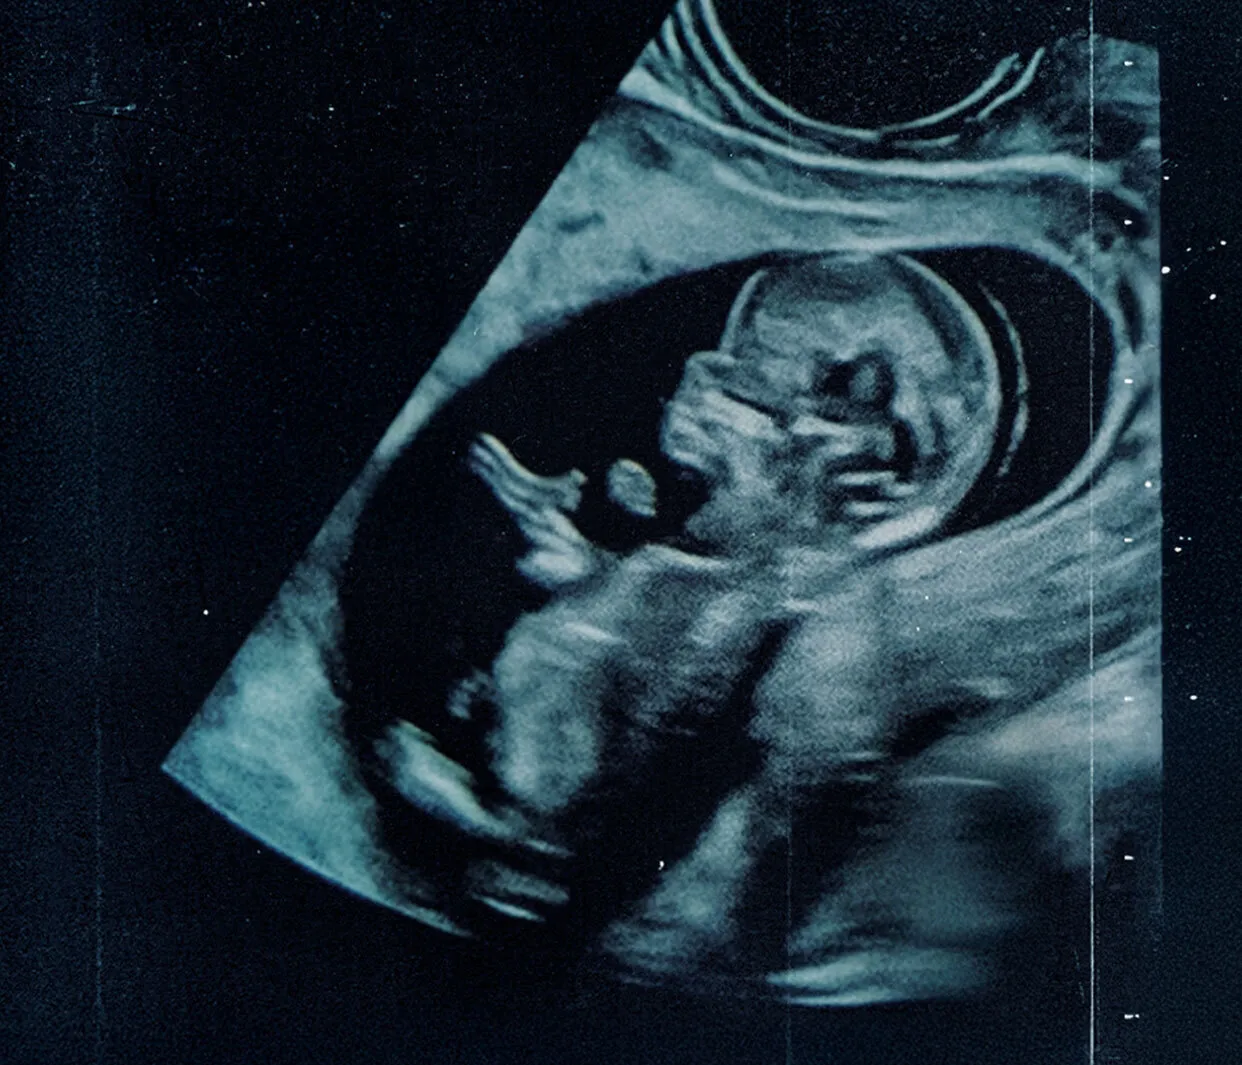

Sinopse: Você já parou para pensar no valor inestimável da vida, diante da escolha mais desafiadora e fascinante da existência? Nosso documentário o convida a confrontar o dilema central da nossa humanidade: como podemos apoiar as mães a fazerem a escolha pela vida e reconhecer a dignidade inegável do ser que ainda pode nascer? É hora de entender por que ser humano vale a pena. Curiosidades: O documentário apresenta uma visão abrangente do debate, ouvindo diversas perspectivas; A série busca entender por que devemos apoiar as mães que se sentem pressionadas e em dúvida; Dirigido por Elton Mesquita. Assista agora: Disponível para assinantes Brasil Paralelo. Experimente e assista hoje mesmo.